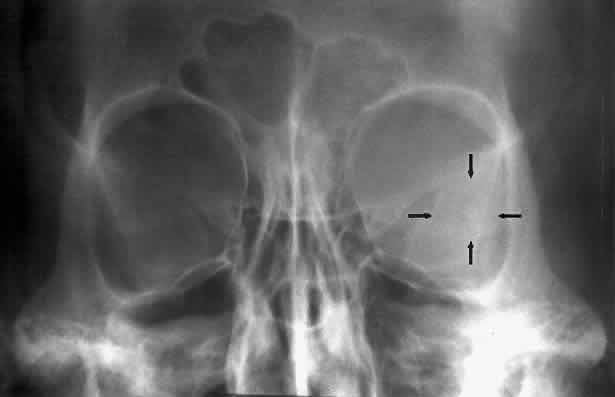

The superior orbital fissure has interpersonal and intrapersonal variations. The fissure should be symmetric, but there is no good measurement that identifies pathology, other than marked asymmetry. The fissure can be enlarged by infraclinoid aneurysm, carotid-cavernous fistulas, pituitary tumors, and meningiomas.26 Less common causes for enlargement include hemangiomas, lymphoma, mucocele of the sphenoid sinus, and neurofibromatosis (Fig. 15).

Fig. 15. Enlargement of the left superior orbital fissure (arrow) by neurofibromatosis. The Caldwell projection gives the best view of this fissure.

The optic foramen should measure 6 mm vertically and 5 mm horizontally. Asymmetry greater than 1 mm or a vertical dimension greater than 6.5 mm is considered abnormal.15,27 Ninety-eight percent of patients have optic canals that vary by less than 1 mm.27 Concentric enlargement of the foramen and optic canal can be seen with optic nerve gliomas, meningiomas, neurofibromatosis, and less commonly an aneurysm of the ophthalmic artery (Fig. 16). A decrease in the optic foramen and canal dimension can be seen in fibrous dysplasia, Paget's disease, hyperostosis secondary to a meningioma, or microphthalmos (Fig. 17, Table 1).

Fig. 16. Oblique apical projections showing the optic foramen. The left optic foramen has concentric enlargement from an optic nerve glioma. The foramen should not have greater than 1 mm of asymmetry.

Fig. 17. Bilateral optic canal compression from fibrous dysplasia. There is diffuse bone thickening in each orbit. Note small size of optic foramen (arrow).